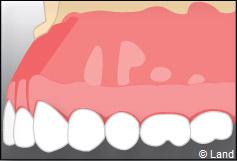

On repositionne le lambeau qui est ensuite suturé, et la radiographie de contrôle peut être prise.

Le fil de suture sera enlevé environ une semaine plus tard.